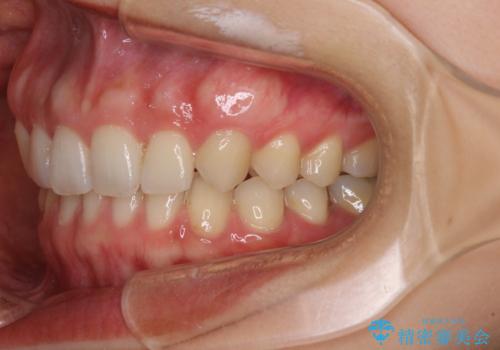

- 前歯の隙間と奥歯の目立つ銀歯を気にして来院された患者様です。

インビザラインにより下顎前歯の隙間を閉じるとともに、奥歯の咬み合わせを改善させることとしました。

矯正治療後には、銀歯のクラウンをセラミッククラウンへ替える補綴治療を行うこととしました。